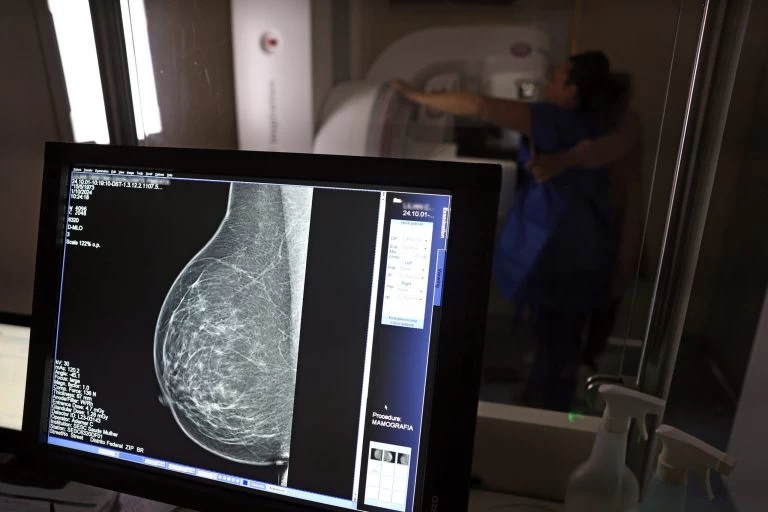

Baixa adesão à mamografia dificulta diagnóstico de câncer de mama; veja hábitos que reduzem fatores de risco

Dados do Panorama do Câncer de Mama revelam que o Brasil possui menos de 24% de cobertura mamográfica, bem abaixo dos 70% recomendados pela Organização Mundial da Saúde (OMS). O estudo também aponta disparidades raciais significativas: 44% das mulheres pretas e pardas recebem diagnóstico tardio, contra 36% das brancas. Especialistas alertam para a necessidade de melhorar o acesso e a conscientização sobre a importância do rastreamento.

Segundo estudos, essas mudanças no estilo de vida podem diminuir em até 30% as chances de desenvolver a doença. Já a prevenção secundária, igualmente crucial, envolve o rastreamento sistemático por meio de mamografias anuais a partir dos 40 anos para a população em geral, com início mais precoce para mulheres que apresentem histórico familiar significativo ou mutações genéticas conhecidas que aumentem o risco. Muitas mulheres enfrentam dificuldades logísticas, como a distância dos serviços de saúde e horários incompatíveis com suas rotinas, o que contribui para baixa adesão, além da falta de conscientização sobre a importância da mamografia.

Ao identificar uma lesão suspeita na mamografia, o próximo passo é realizar uma biópsia para confirmação histológica. Uma vez diagnosticado, o tratamento pode incluir cirurgia (desde abordagens conservadoras até mastectomia), hormonioterapia, quimioterapia, radioterapia ou imunoterapia, dependendo do tipo e estágio do tumor.